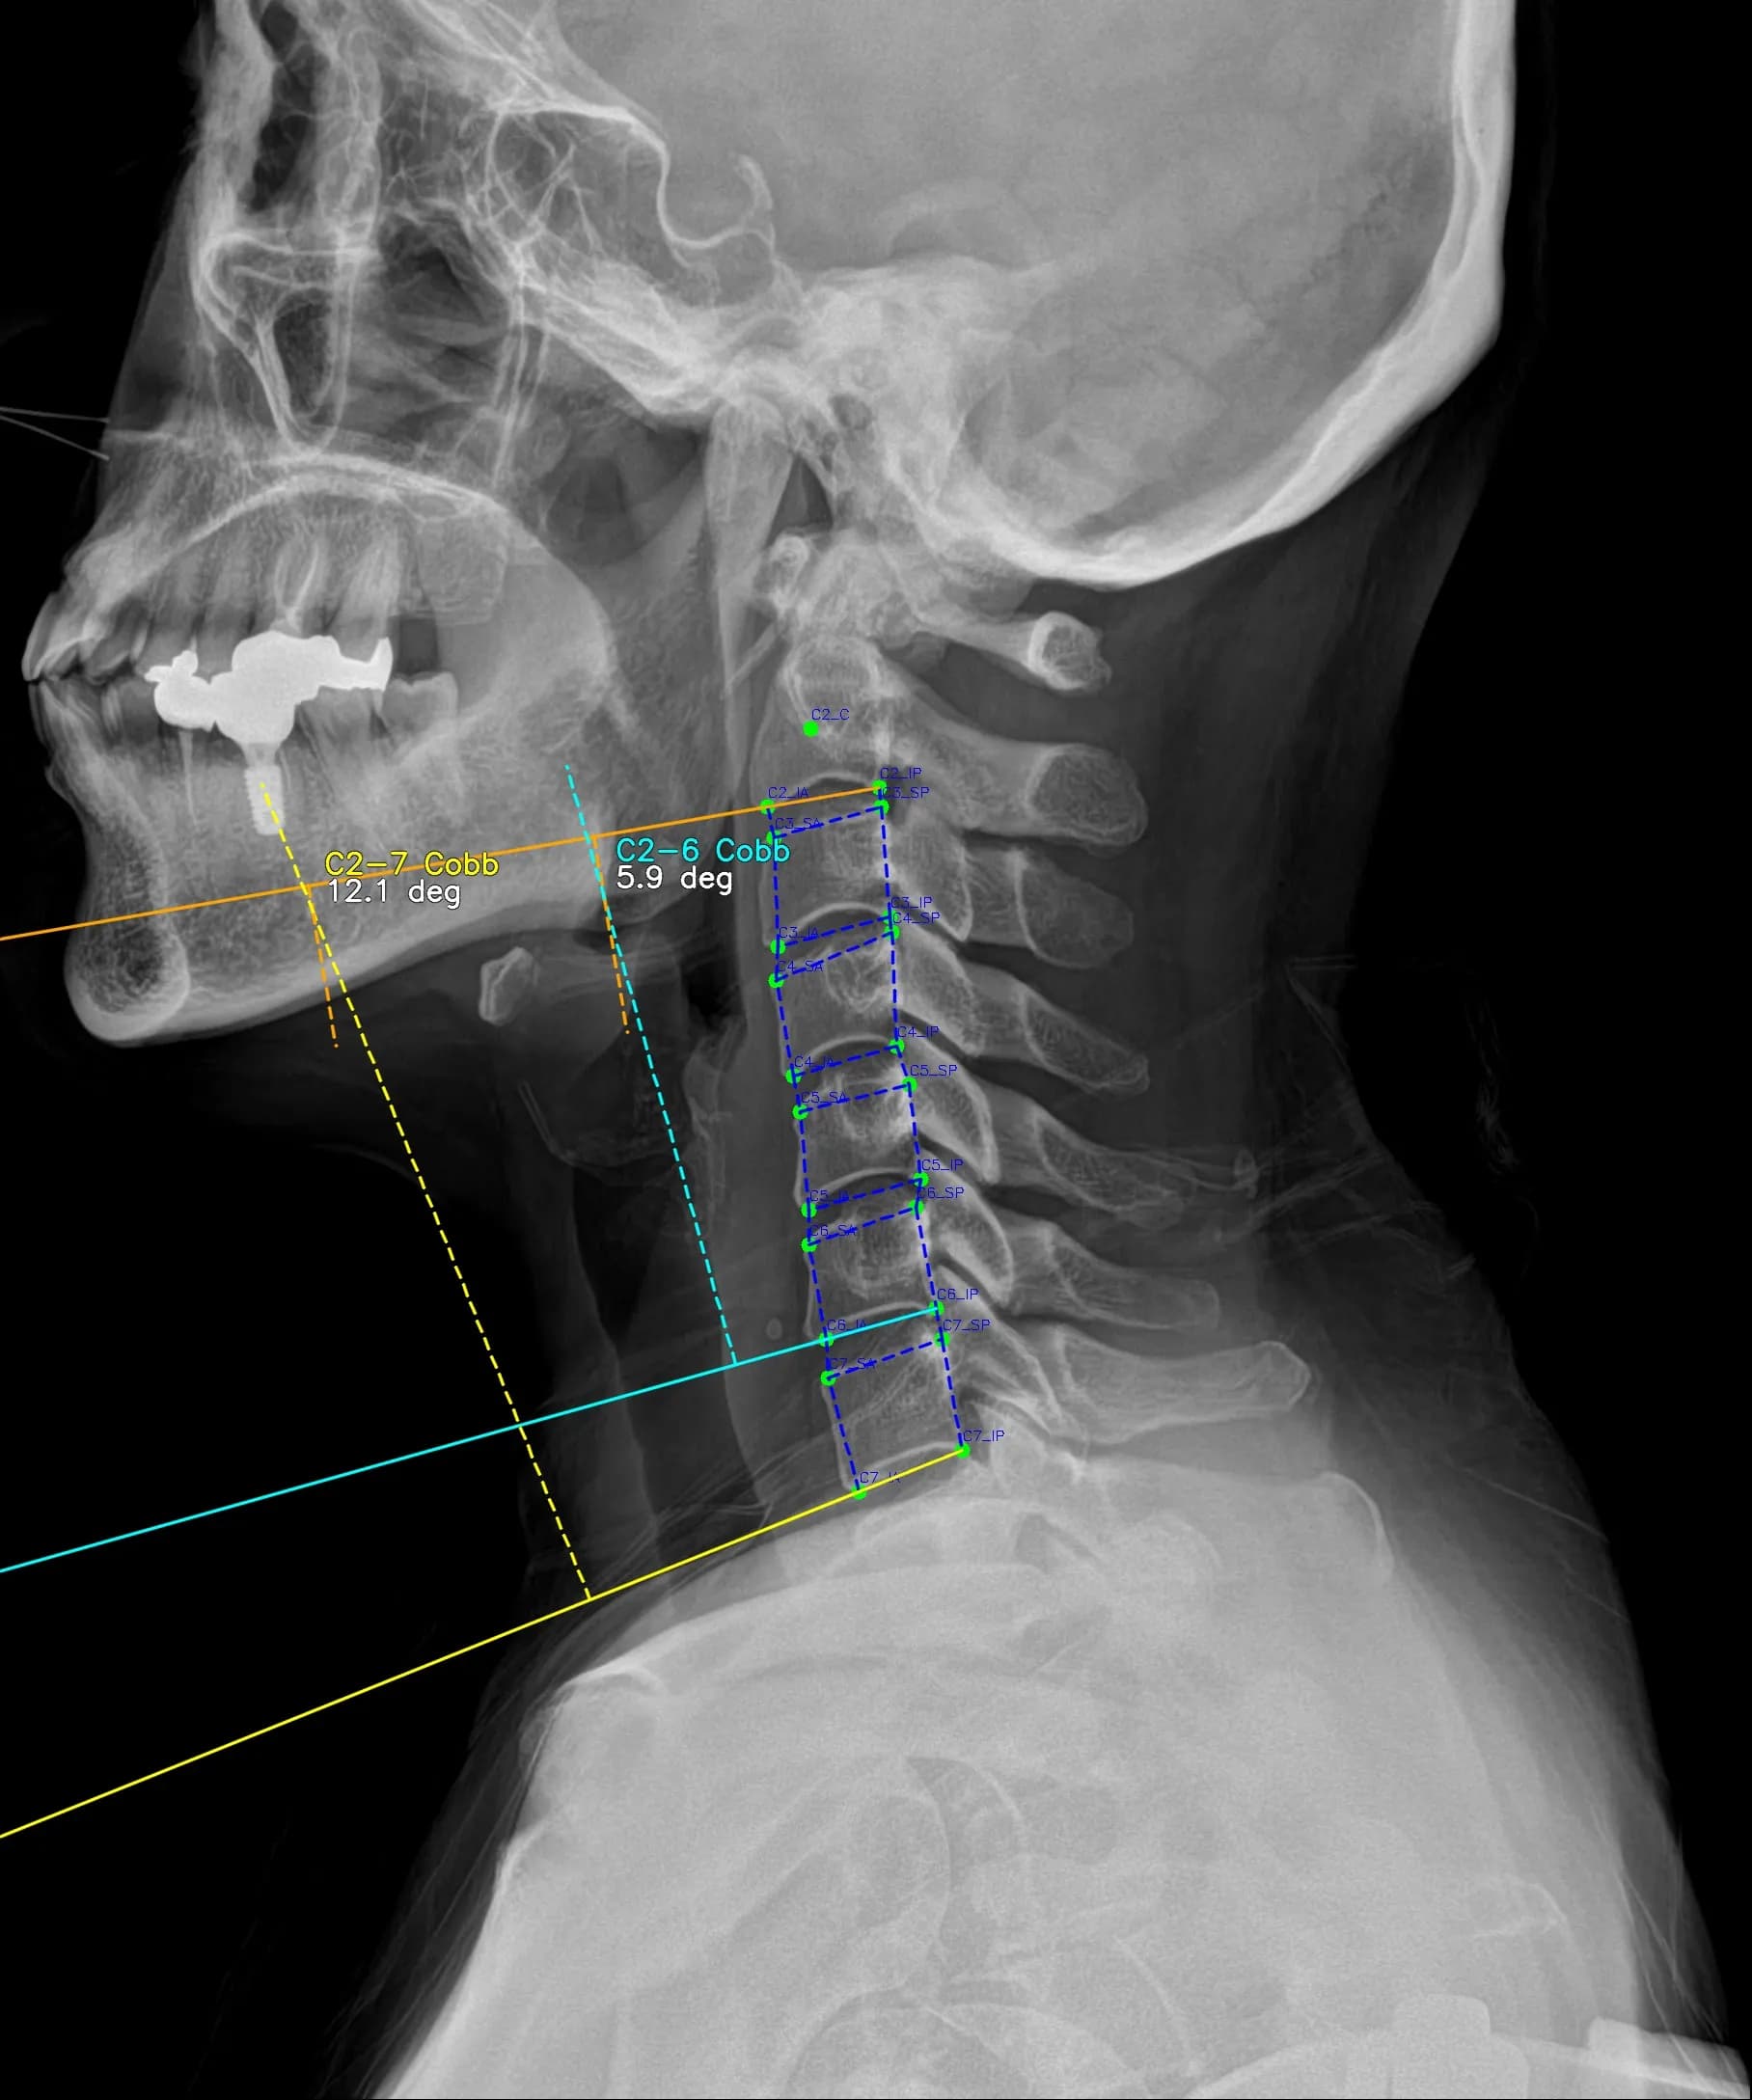

Musculoskeletal X-ray AI Analysis

부위를 클릭하여 결과 이미지를 확인하실 수 있습니다.